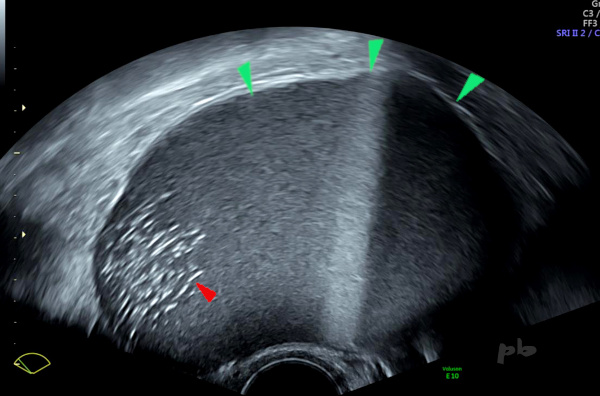

13 – Diagnostic différentiel – Kyste dermoïde

Echographie

On retrouve plusieurs niveaux liquide-liquide (►), plus rarement observés dans les kystes dermoïdes par rapport aux kystes endométriosiques.

En déclive, visualisation d’échos intenses (►) très évocateurs de l’origine dermoïde.